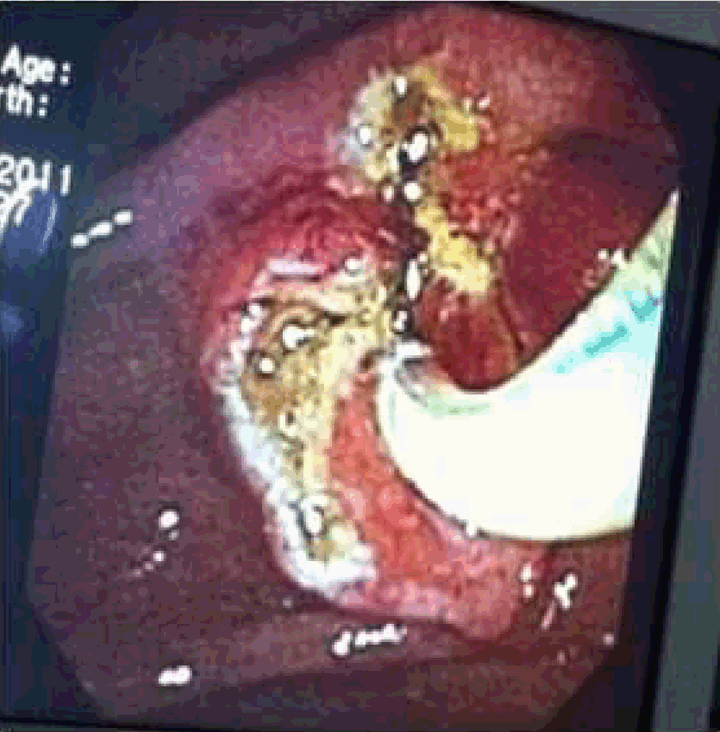

A 43-year-old female presented with severe right upper quadrant abdominal pain, nausea, vomiting and diarrhea for four days. Three years ago, she was admitted for cholecystitis, cholelithiasis and cholangitis requiring an endoscopic retrograde cholangiopancreatography (ERCP) with plastic stent placement for drainage. Unfortunately, the patient was lost to follow-up after initial plastic stent placement. On admission, she was afebrile and her liver function tests were normal. The ERCP was performed which revealed the distal end of the biliary stent, perforating proximal to the periampullary area causing a large choledochoduodenal fistula (Figure 1). The guidewire was successfully negotiated through the native papilla as well as the fistulous tract. No obstruction, mass or stone was noted. A sphincterotomy was done through the fistula (Figure 2) and through the actual sphincter at the ampulla (Figure 3). The sump was opened, swept clean with removal of abundant debris. Her abdominal pain completely resolved and patient clinically improved within 24 hours after the procedure. | ||||||